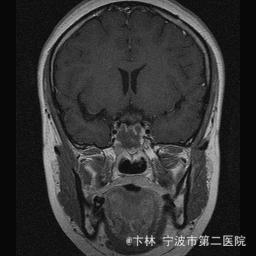

40岁女性,因“双眼视力下降三月余伴停经1个月余”入院。 患者三月前无明显诱因下出现双眼视力下降,视物模糊,尤以左眼为甚,只能近距离看到手动,无头痛、头晕,无恶心、呕吐,无视物旋转,无行走困难等不适,患者曾在某眼科医院就诊治疗,考虑为双眼视神经炎,予以营养,补液对症等治疗(具体不详),情况不见好转,近一月来患者月经停止,来我院神经外科门诊,予以查头颅CT,头颅MRI,提示“垂体大腺瘤”,为求进一步治疗收住入院

予以完善血,尿,粪常规检查,及凝血功能全套,输血功能全套及垂体功能全套,蝶鞍冠状CT等术前检查措施,行经蝶入路垂体瘤切除术。术后予以对症,补液,调节血电解质等治疗,患者视力明显改善,复查头颅MRI提示肿瘤基本全切,一周后患者出院。

此病人颅内垂体瘤体积较大,突破鞍隔压迫视交叉,故患者视力视野障碍为首发症状,该肿瘤主体有大部分向蝶窦腔生长,因此采用经蝶手术入路,肿瘤切除满意,术后患者视力视野恢复满意,。